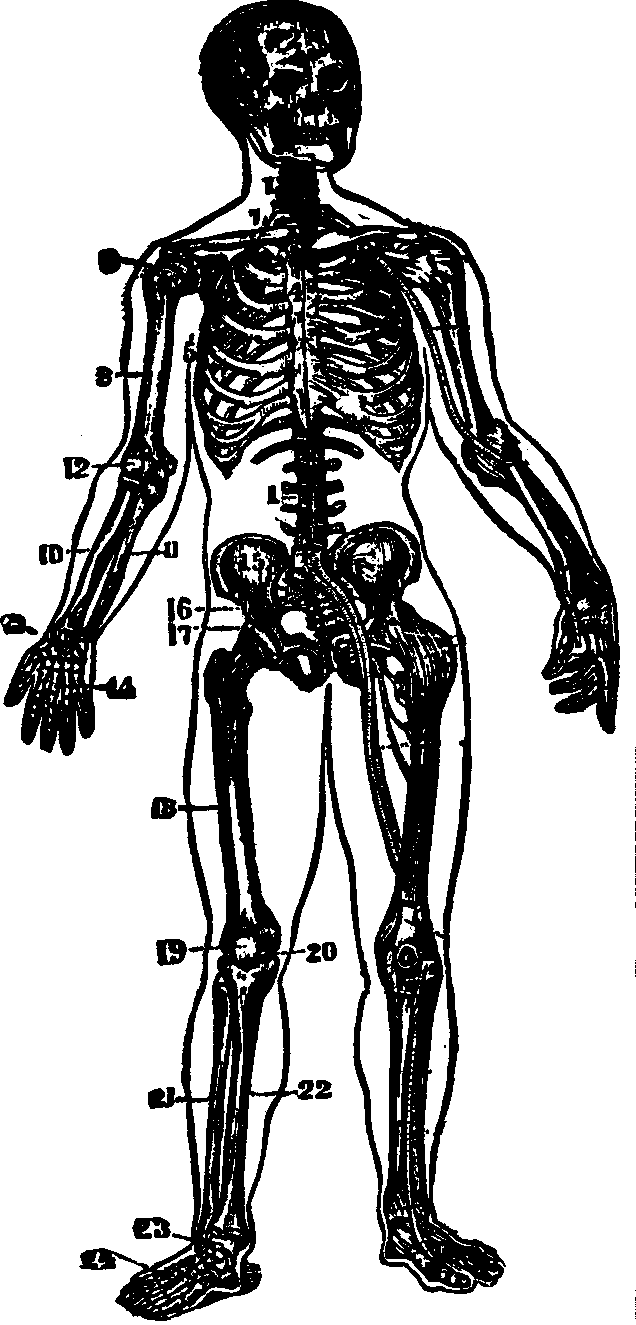

Fig. 16. 1. Portions of

the backbone. 2. Cranial bones. 4. Breast-bone. 5. Ribs.

7. Collar-bone. 8. Arm-bone (humerus). 9.

Shoulder-joint. 10, 11. Bones of the fore-arm (ulna and radius).

12. Elbow-joint. 13. Wrist-joint. 14. Bones of the

hand. 15, 16. Pelvic bones. 17. Hip-joint. 18. Femur.

19, 20. Bones of the knee-joint. 21, 22. Fibula and tibia.

23. Ankle bone. 24. Bones of the foot.

The Bones of the Upper Extremities are sixty-four in number, and

are classified as follows: The Scapula, [pg 26]Clavicle, Humerus, Ulna,

Radius, Carpus, Metacarpus, and Phalanges. The Scapula, or

shoulder-blade, is an irregular, thin, triangular bone, situated at the

posterior part of the shoulder, and attached to the upper and back part of

the chest. The Clavicle, or collar-bone, is located at the upper

part of the chest, between the sternum and scapula, and connects with both.

Its form resembles that of the italic letter f, and it prevents the

arms from sliding forward. The Humerus, the first bone of the arm,

is long, cylindrical, and situated between the scapula and fore-arm. The

Ulna is nearly parallel with the radius, and situated on the inner

side of the fore-arm. It is the longer and larger of the two bones, and in

its articulation with the humerus, forms a perfect hinge-joint. The

Radius, so called from its resemblance to a spoke, is on the outer

side of the fore-arm, and articulates with the bones of the wrist, forming

a joint. The ulna and radius also articulate with each other at their

extremities. The Carpus, or wrist, consists of eight bones, arranged

in two rows. The Metacarpus, or palm of the hand, is composed of

five bones [pg

27]situated between the carpus and fingers. The Phalanges,

fourteen in number, are the bones of the fingers and thumb, the fingers

each having three and the thumb two.

The Bones of the Lower Extremities, sixty in number, are classed

as follows: The Femur, Patella, Tibia, Fibula, Tarsus, Metatarsus, and

Phalanges. The Femur, or thigh-bone, is the longest bone in the

body. It has a large round head, which is received into the acetabulum,

thus affording a good illustration of a ball and socket joint. The

Patella, or knee-pan, is the most complicated articulation of the

body. It is of a round form, connects with the tibia by means of a strong

ligament, and serves to protect the front of the joint, and to increase the

leverage of the muscles attached to it, by causing them to act at a greater

angle. The Tibia, or shin bone, is enlarged at each extremity and

articulates with the femur above and the astragalus, the upper bone of the

tarsus, below. The Fibula, the small bone of the leg, is situated on

the outer side of the tibia, and is firmly bound to it at each extremity.

The Tarsus, or instep, is composed of seven bones, and corresponds

to the carpus of the upper extremities. The Metatarsus, the middle

of the foot, bears a dose resemblance to the metacarpus, and consists of

five bones situated between the tarsus and the phalanges. The tarsal and

the metatarsal bones are so united as to give an arched appearance to the

foot, thus imparting elasticity. The Phalanges, the toes, consist of

fourteen bones, arranged in a manner similar to that of the fingers.